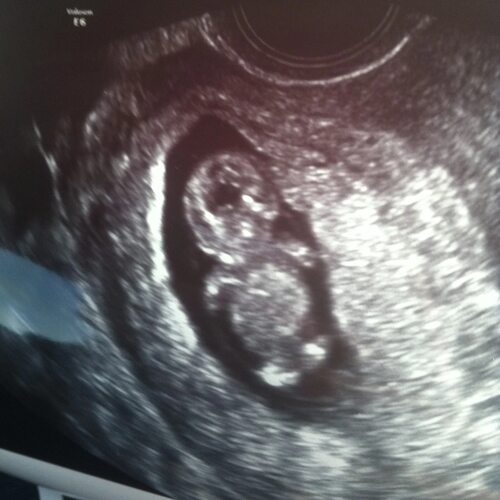

На 10 неделе беременности происходят значительные изменения в развитии плода. С помощью узи можно увидеть прогресс и следить за его развитием.

Фото плода на 10 неделе беременности

Ниже представлены различные фотографии, сделанные с помощью узи на 10 неделе беременности. Они позволяют родителям увидеть, как прогрессирует развитие ребенка в этот период: